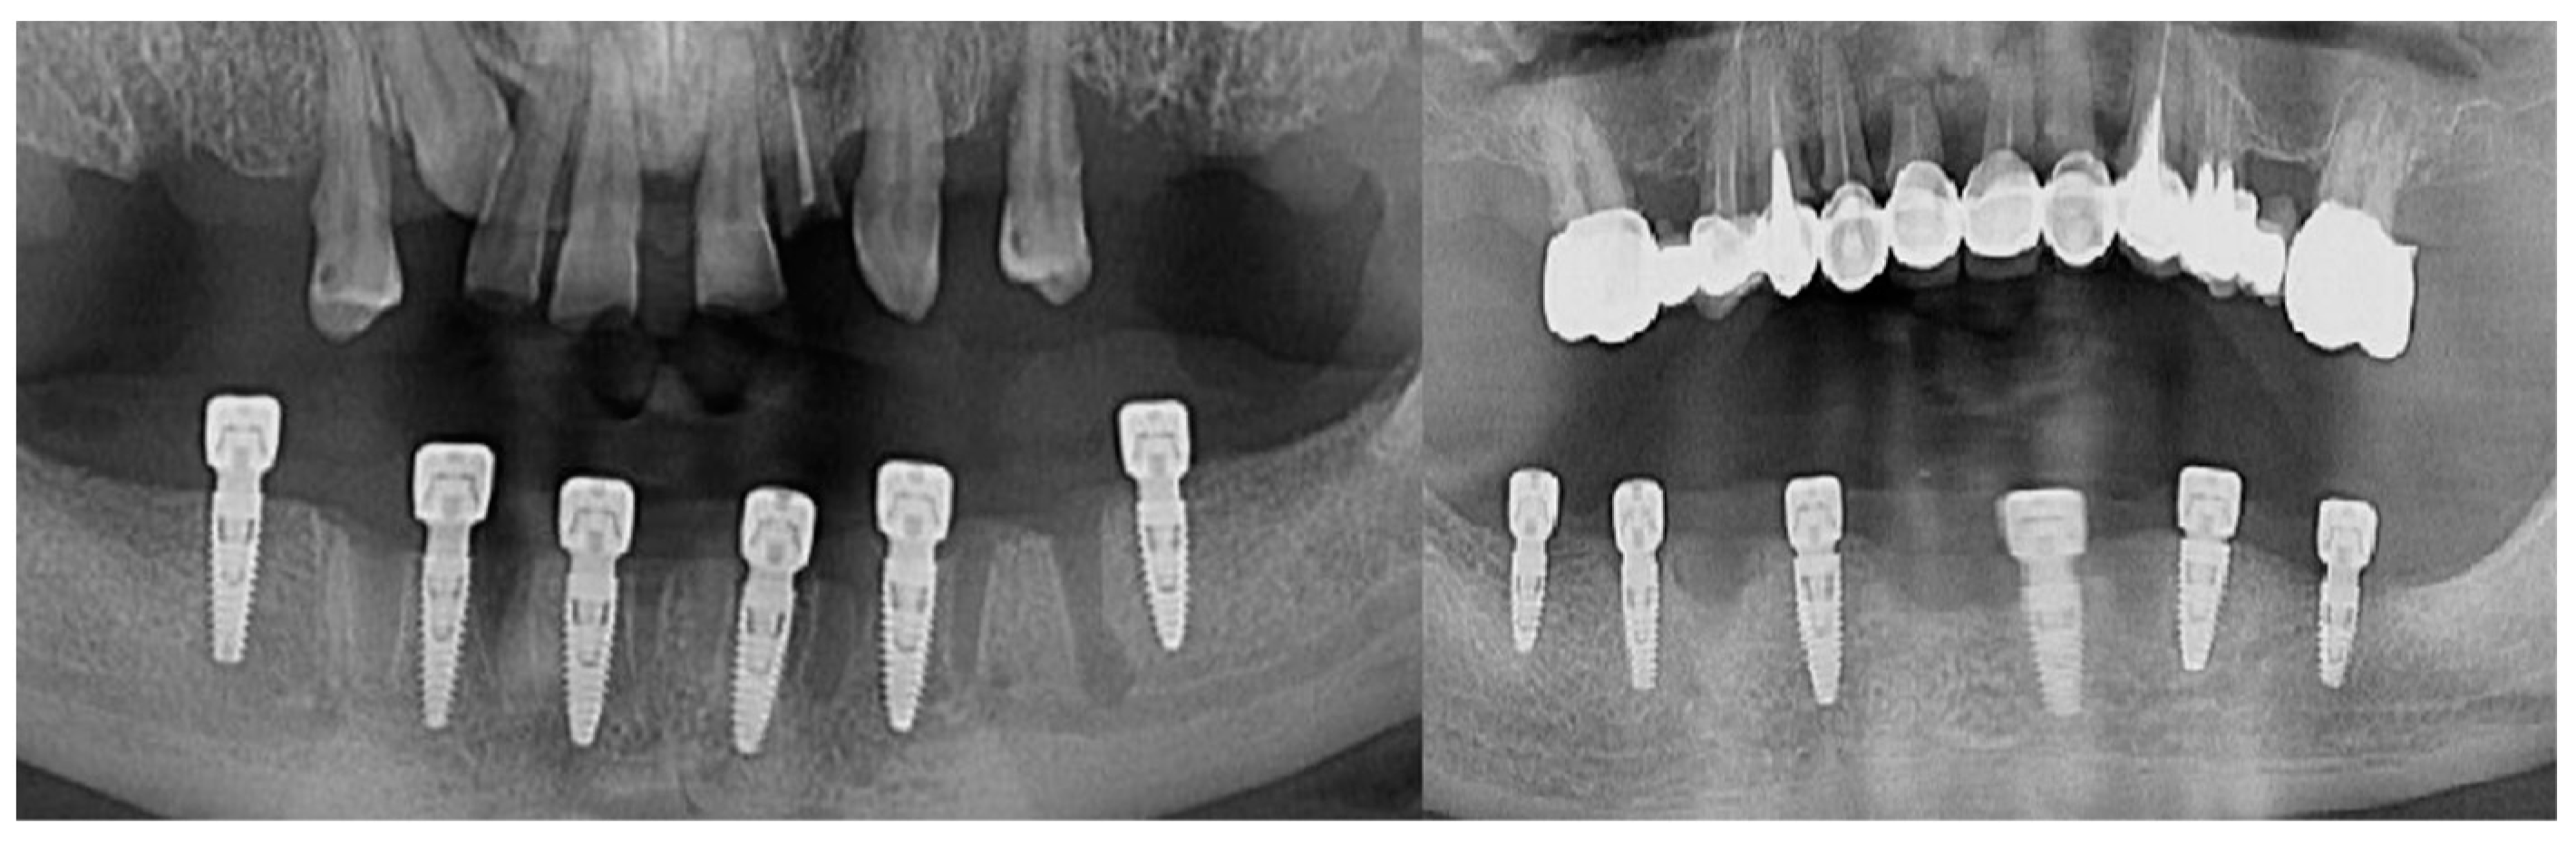

Intraoperatively, the dental implants were screwed into the alveolar bone according to the manufacturers’ indications, being applied over the dental implant with either a covering screw or healing abutment or multiunit abutment (Figure 1). The postoperative wound was sutured with Dafilon™ 4/0 suture thread (BBraun Hessen, Germany BBraun, Spangenberg, Germany) and Dafilon™ 5/0 suture thread (BBraun Hessen, Germany BBraun, Spangenberg, Germany).

Figure 1.

Radiological images presenting different clinical cases included in the study.